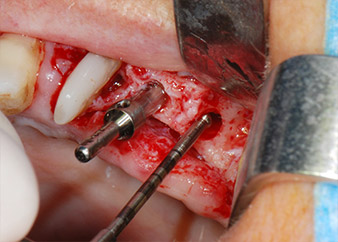

IImplant beds were prepared at sites 25 and 26 with rotary instruments, used in a contra-angle handpiece with a 20 : 1 transmission ratio with an updated powerful implant motor (Implantmed, W&H) (Fig. 8).

The final preparation next to the sinus was again carried out with a piezoelectric instrument (Piezomed, insert S2).